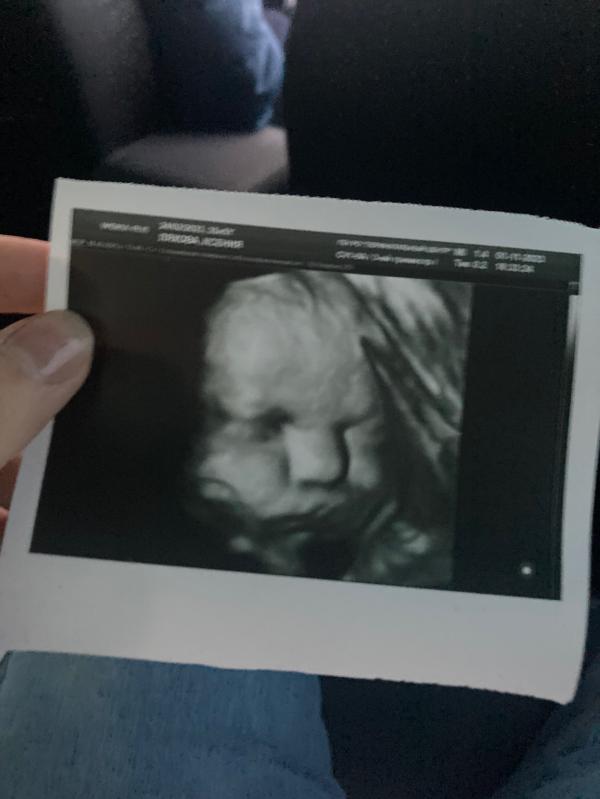

💟Еще день и начнется 37-ая неделя

💟Сегодня опять делали УЗИ

-ВЕС 2360

-35,5 недель

💟Откормила хомячка😊